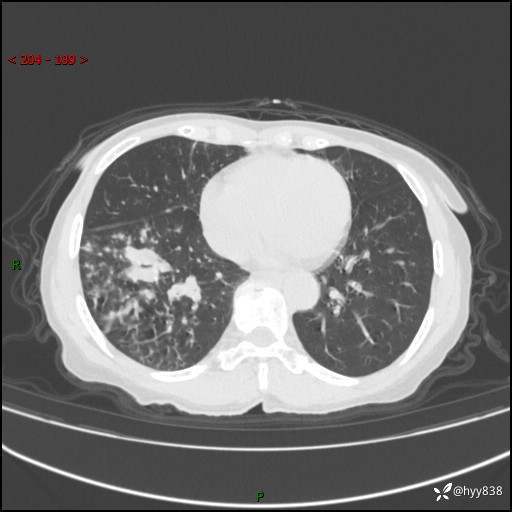

患者性别:男

患者年龄:69岁

简要病史:咳嗽咳痰2月,夜间加重

临床诊断:感染

胸部CT平扫